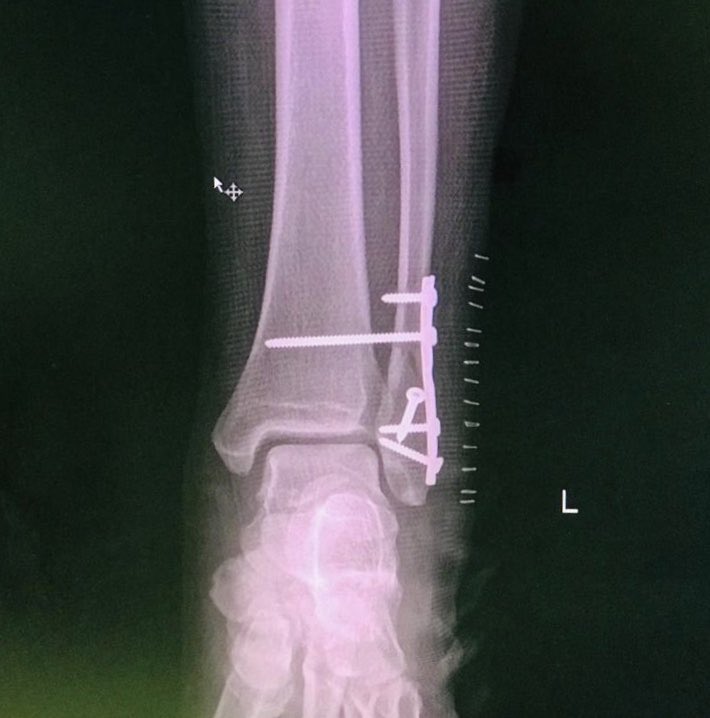

٣-ذهبت للموعد و اعادو لي الإشاعة و ذكر لي الجراح ان الكسر موجود و عندنا خيارين واحد منهم تجلس على الجبس بدون عملية و الثاني نعمل عملية نثبت الكسر و كل الحلين صحيح و فترت عدم وقوفك نفسها ٦-٨ اسابع بسبب قطع اربطه الكاحل

قلت له انت ايش رأيك قال لي عملية و لكن انت قرر فقلت اذن عمليه

٥-تمت العمليه و لله الحمد و شكرا و جزى الله خيراً لكل من حملني و انزلني و رافقني من سريري و حتى سرير غرفة العمليات و لفريق التخدير و فريق جراحة العظام

أخيرا الشكر لله ثم لأخي الدكتور وائل طه إستشاري جراحة العظام و الإصابات على ماقام به و لا أملك له إلا الدعاء و من المفارقات الجميله أن الدكتورة أفنان الفريدي التي ساعدت في العملية هي إحدى أميز خريجات كليتنا و تشرفت أني درستها في يوم ما و بحول الله ستكون إستشارية جراحة عظام كبيرة